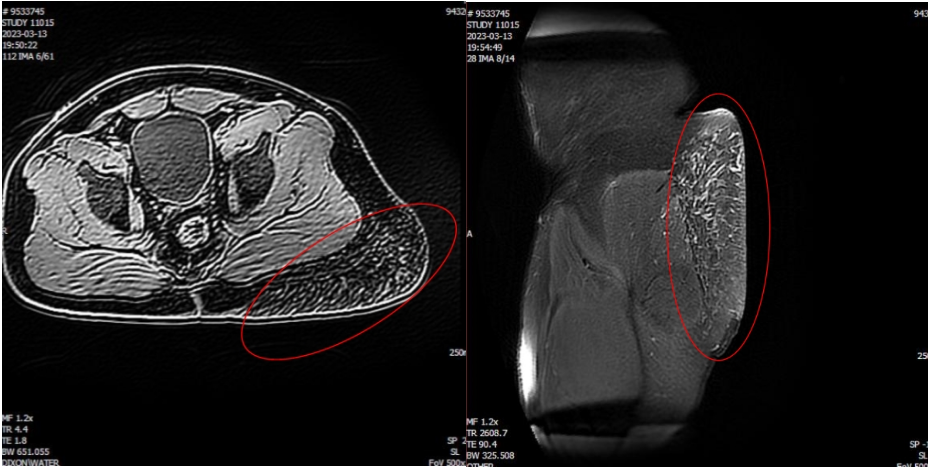

患者男性,28岁,出生时发现左侧臀部拳头大小暗红色皮肤斑块,斑块逐渐蔓延增大并隆起,严重影响正常生活。患者入院后,检查发现左侧臀部可见大小约25cm×30cm×8cm隆起的巨大肿瘤,局部皮温高,MRI检查显示该肿瘤与深部肌膜粘连紧密,有10多支粗大的血管自深部肌肉穿过肌膜滋养肿瘤。

因血管瘤体积巨大,其来自深部的滋养血管粗大、数量较多,出血风险极大。经充分讨论后,刘毅教授团队制定了周密细致的方案,在全麻下实施巨大血管瘤切除术。术中,逐一结扎、缝扎滋养血管,完整切除2.5公斤重的瘤体,并自背部切取大张中厚皮片移植修复创面。手术历时2小时,术后患者恢复良好,创面植皮100%成活,现已康复出院。